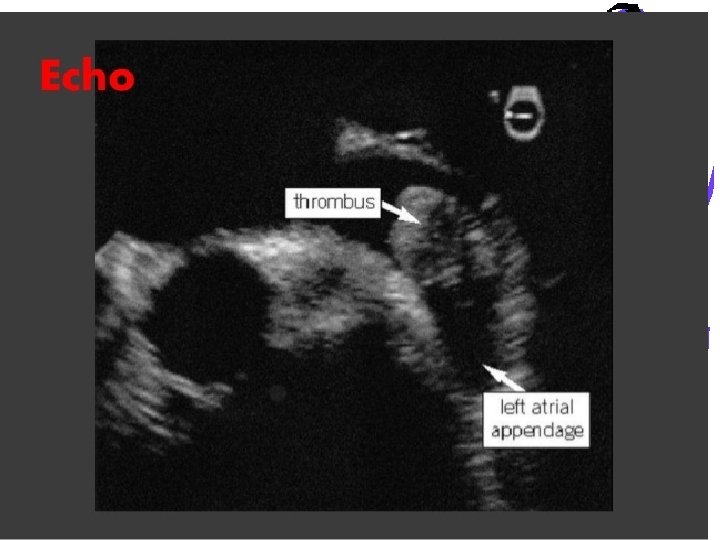

Left atrial appendage occlusion • Watchman device only FDA approved percutaneous LAA closure device • semi-spherical nitinol frame with a polyethylene terephthalate membrane coating • deployed transseptally using a dedicated 14 Fr sheath usually under transesophageal echocardiography and fluoroscopic guidance.